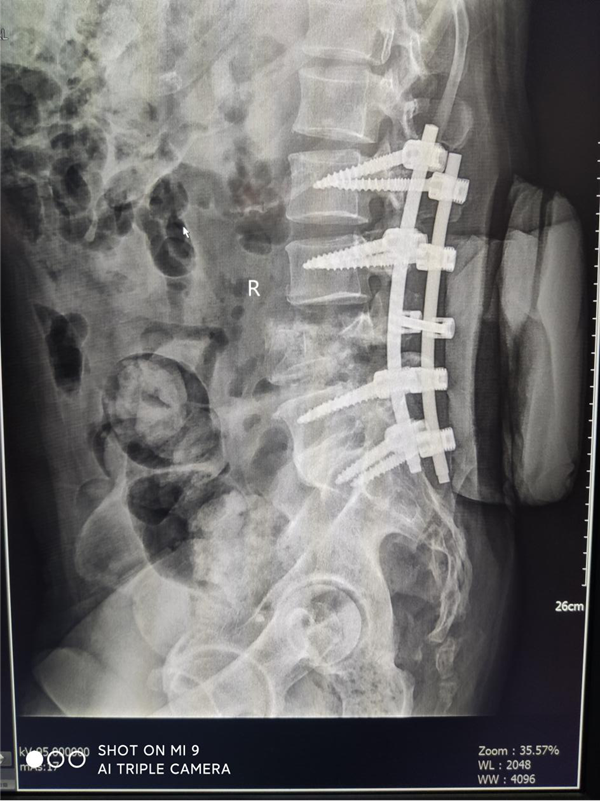

患者刘某,男,55岁,高处坠落致腰部疼痛伴双下肢麻木16小时主诉入院,由于腰部先着地,当时即觉腰部剧烈疼痛伴双下肢麻木和大小便失禁,伤后无昏迷抽搐,无腹痛腹胀,可回忆受伤时情况,伤后未作特殊处理,遂由家属送至我院急诊,查腰椎MRI:腰4椎体爆裂性骨折并继发椎体滑脱,为进一步治疗,急诊收住骨三科。

刘某家属找到了我院骨三科的张纯教授。张教授经过详细了解患者的病情,并判断这是一例严重复杂的脊髓损伤,需要立马进行手术治疗。于是为刘某联系了病房,结合患者年龄大、手术创伤大、出血风险高等特点,经过多次科室讨论及多科室疑难病例会诊,积极联合危重医学科、麻醉科、输血科等相关科室共同制定了周密的手术方案。根据患者病情制定了详细的手术计划及围手术期治疗方案。经过严密的手术前准备,以张纯主任医师为主刀、王伟卓主治医师和黄思华博士为助手,吴刚副主任医师、罗斌医师为麻醉医师,殷敏、马霞为配合护士,黄亚娟、王芳医师为术中诱发电位监护医师的手术团队努力下,手术顺利完成,切开复位内固定保护了严重受伤的脊髓,并进行了脊柱的重建。